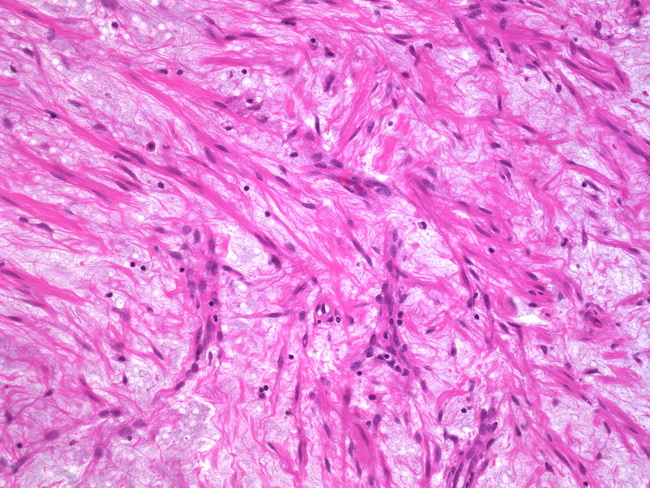

Webpathology.com: A Collection Of Surgical Pathology Images

www.webpathology.com

www.webpathology.com

leiomyoma uterus myxoid webpathology comments pathology

Webpathology.com: A Collection Of Surgical Pathology Images

webpathology.com

webpathology.com

leiomyoma myxoid change pathology webpathology comments

Webpathology.com: A Collection Of Surgical Pathology Images

www.webpathology.com

www.webpathology.com

uterus myxoid leiomyoma muscle smooth webpathology pathology fibrillary cells nuclei comments